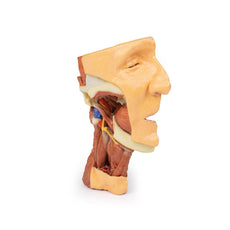

3D Printed Superficial Facial Nerves & Parotid Gland

This 3D model presents the superficial anatomy of the face and head, and compliments the superficial facial anatomy

of our HW 44 model with a more expanded dissection across the scalp and occipital regions.

The superficial

neurovascular and muscular structures in the face largely mirror the structures described in reference to our HW 44

specimen (see description), although the terminal branches of the facial nerve (CNVII) can be largely followed

across a longer course from the parotid gland and the platysma muscle has been retained superficial to the mandible

and extends towards the neck.

In contrast to the HW 44 specimen, this model has a more expansive superficial

dissection inferior to the external ear and across the posterior scalp and occipital region. This allows for an

expanded appreciation of the neurovascular distribution of the supraorbital and supratrochlear nerves and arties

with the superficial temporal artery. Inferior to the ear, the retromandibular vein has been exposed with the

ascending fibres of the great auricular nerve on its superficial surface (and further branches of this nerve on the

surface of the sternocleidomastoid muscle). At the posterior border of the sternocleidomastoid muscle the lesser

occipital nerve is just preserved, near the exiting and ascension of the occipital artery and vein near the

trapezius muscle towards the posterior scalp. Surrounding the external ear are fibres of the auricularis superior

and posterior muscles. Near the margin of the dissection window posteriorly the deep fibres of the occiptalis muscle

can be seen integrated into the epicranius (occipitofrontalis) muscle.